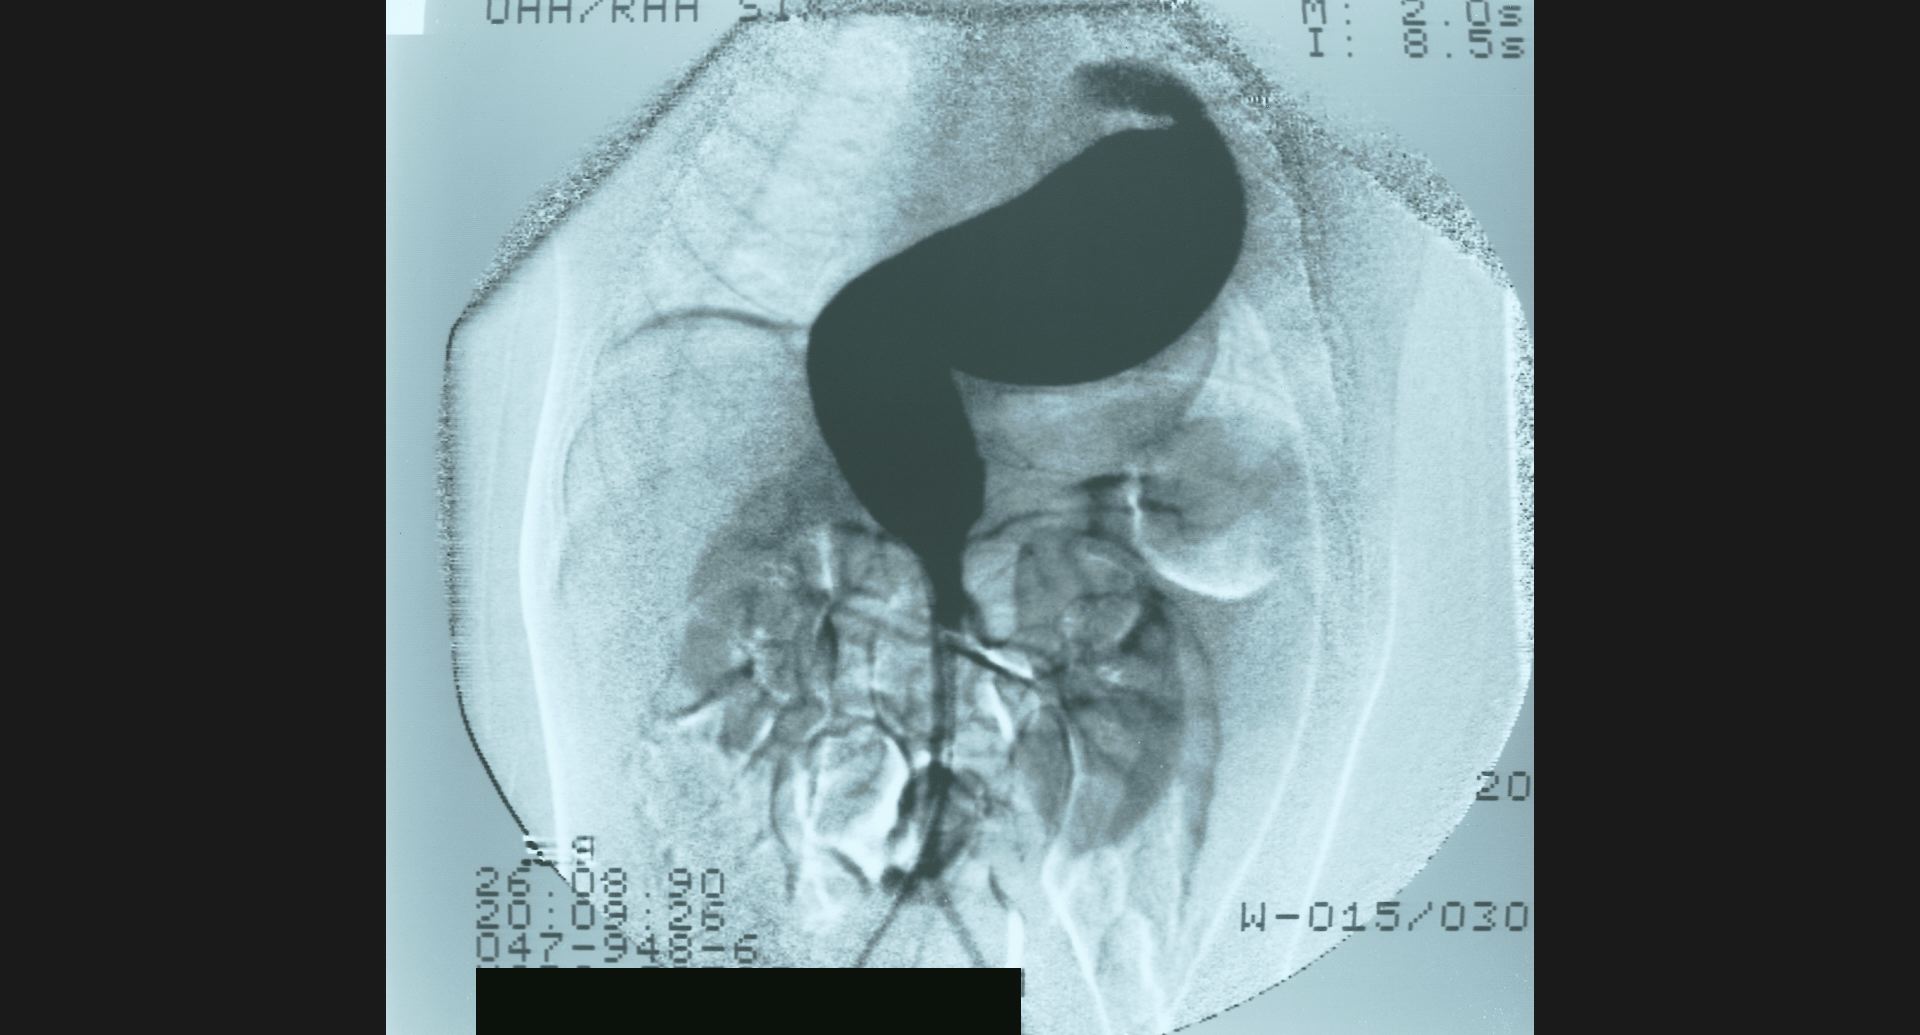

fig.10(99KB)

:SMA thrombosis (angiography)閉塞部位。腸管壁の細かい動脈。